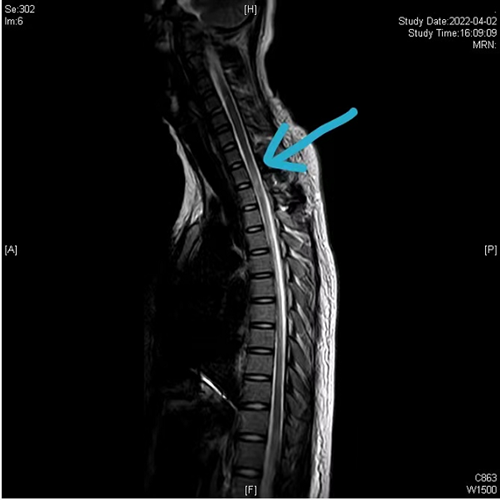

术后颈胸椎磁共振(蓝色箭头提示血肿已完全清除,脊髓通畅)

入院后前5天,经严格卧床保守治疗后,孙温溪双下肢麻木的情况一天天好转,然而到了第6天早晨,孙温溪突然出现胸背部剧烈疼痛,双下肢失去了感觉和活动功能,脊柱外科团队立即安排神经内科、神经外科等多学科会诊,制定紧急手术方案——后路颈7-胸2椎板切除、血肿清除,椎管减压术。手术非常顺利,术后当天孙温溪双下肢就恢复了部分感觉活动,经过针灸、高压氧、功能锻炼等促神经功能恢复治疗后,孙温溪的双下肢麻木症状明显缓解,目前在香港马会app康复科继续理疗训练。